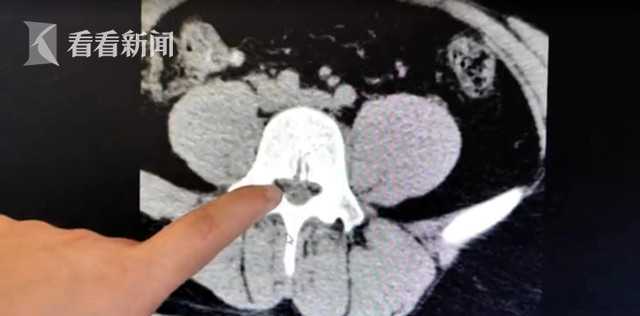

腰部的疼痛让小王在家里已难以忍受,家人赶紧将他送到医院,检查的时候,医生发现肌肉已经开始出现溃烂的迹象。经过详细检查,医生诊断其实就是常见的腰椎间盘突出症。